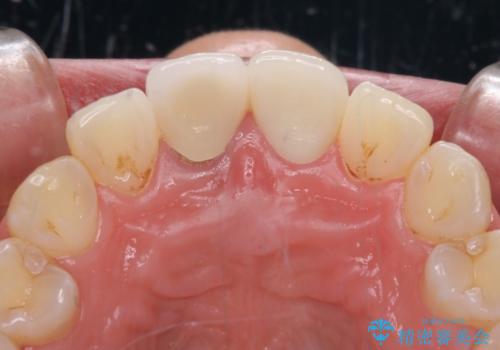

目立つ前歯の詰め物 オーダーメイドのセラミッククラウンで審美的に仕上げる

反対側同名歯にセラミッククラウンが装着されていたため、そちらのクラウンと形態や色彩を揃えるようオーダーメイドタイプのオールセラミッククラウンにて補綴することとしました。

2本同時に処置をし、2本とも明るい色合いにすることをお勧めしましたが、今回は1歯のみとしました。

左右のバランスが取れ、患者様には大変満足していただきました。